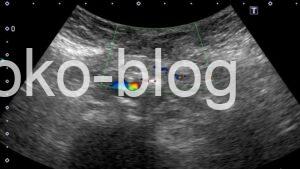

カラードプラで観察してみましたがのらず

腸管が皮下に見えるってことはヘルニアかな、カラーものらないから嵌頓の可能性もあるかなと医師に報告。

- 腸拡張は認めない

- パルスドプラはSMIが装備されていないので評価が難しい

微妙ですが、「腸拡張がない」という時点で絞扼性ではないと判断して良かったのかなとも。

畠先生は「カラーがのる≒血流がある」とも仰っていたし…そして「腸閉塞は簡単」とも…まだまだ修行が足りないと痛感しました。